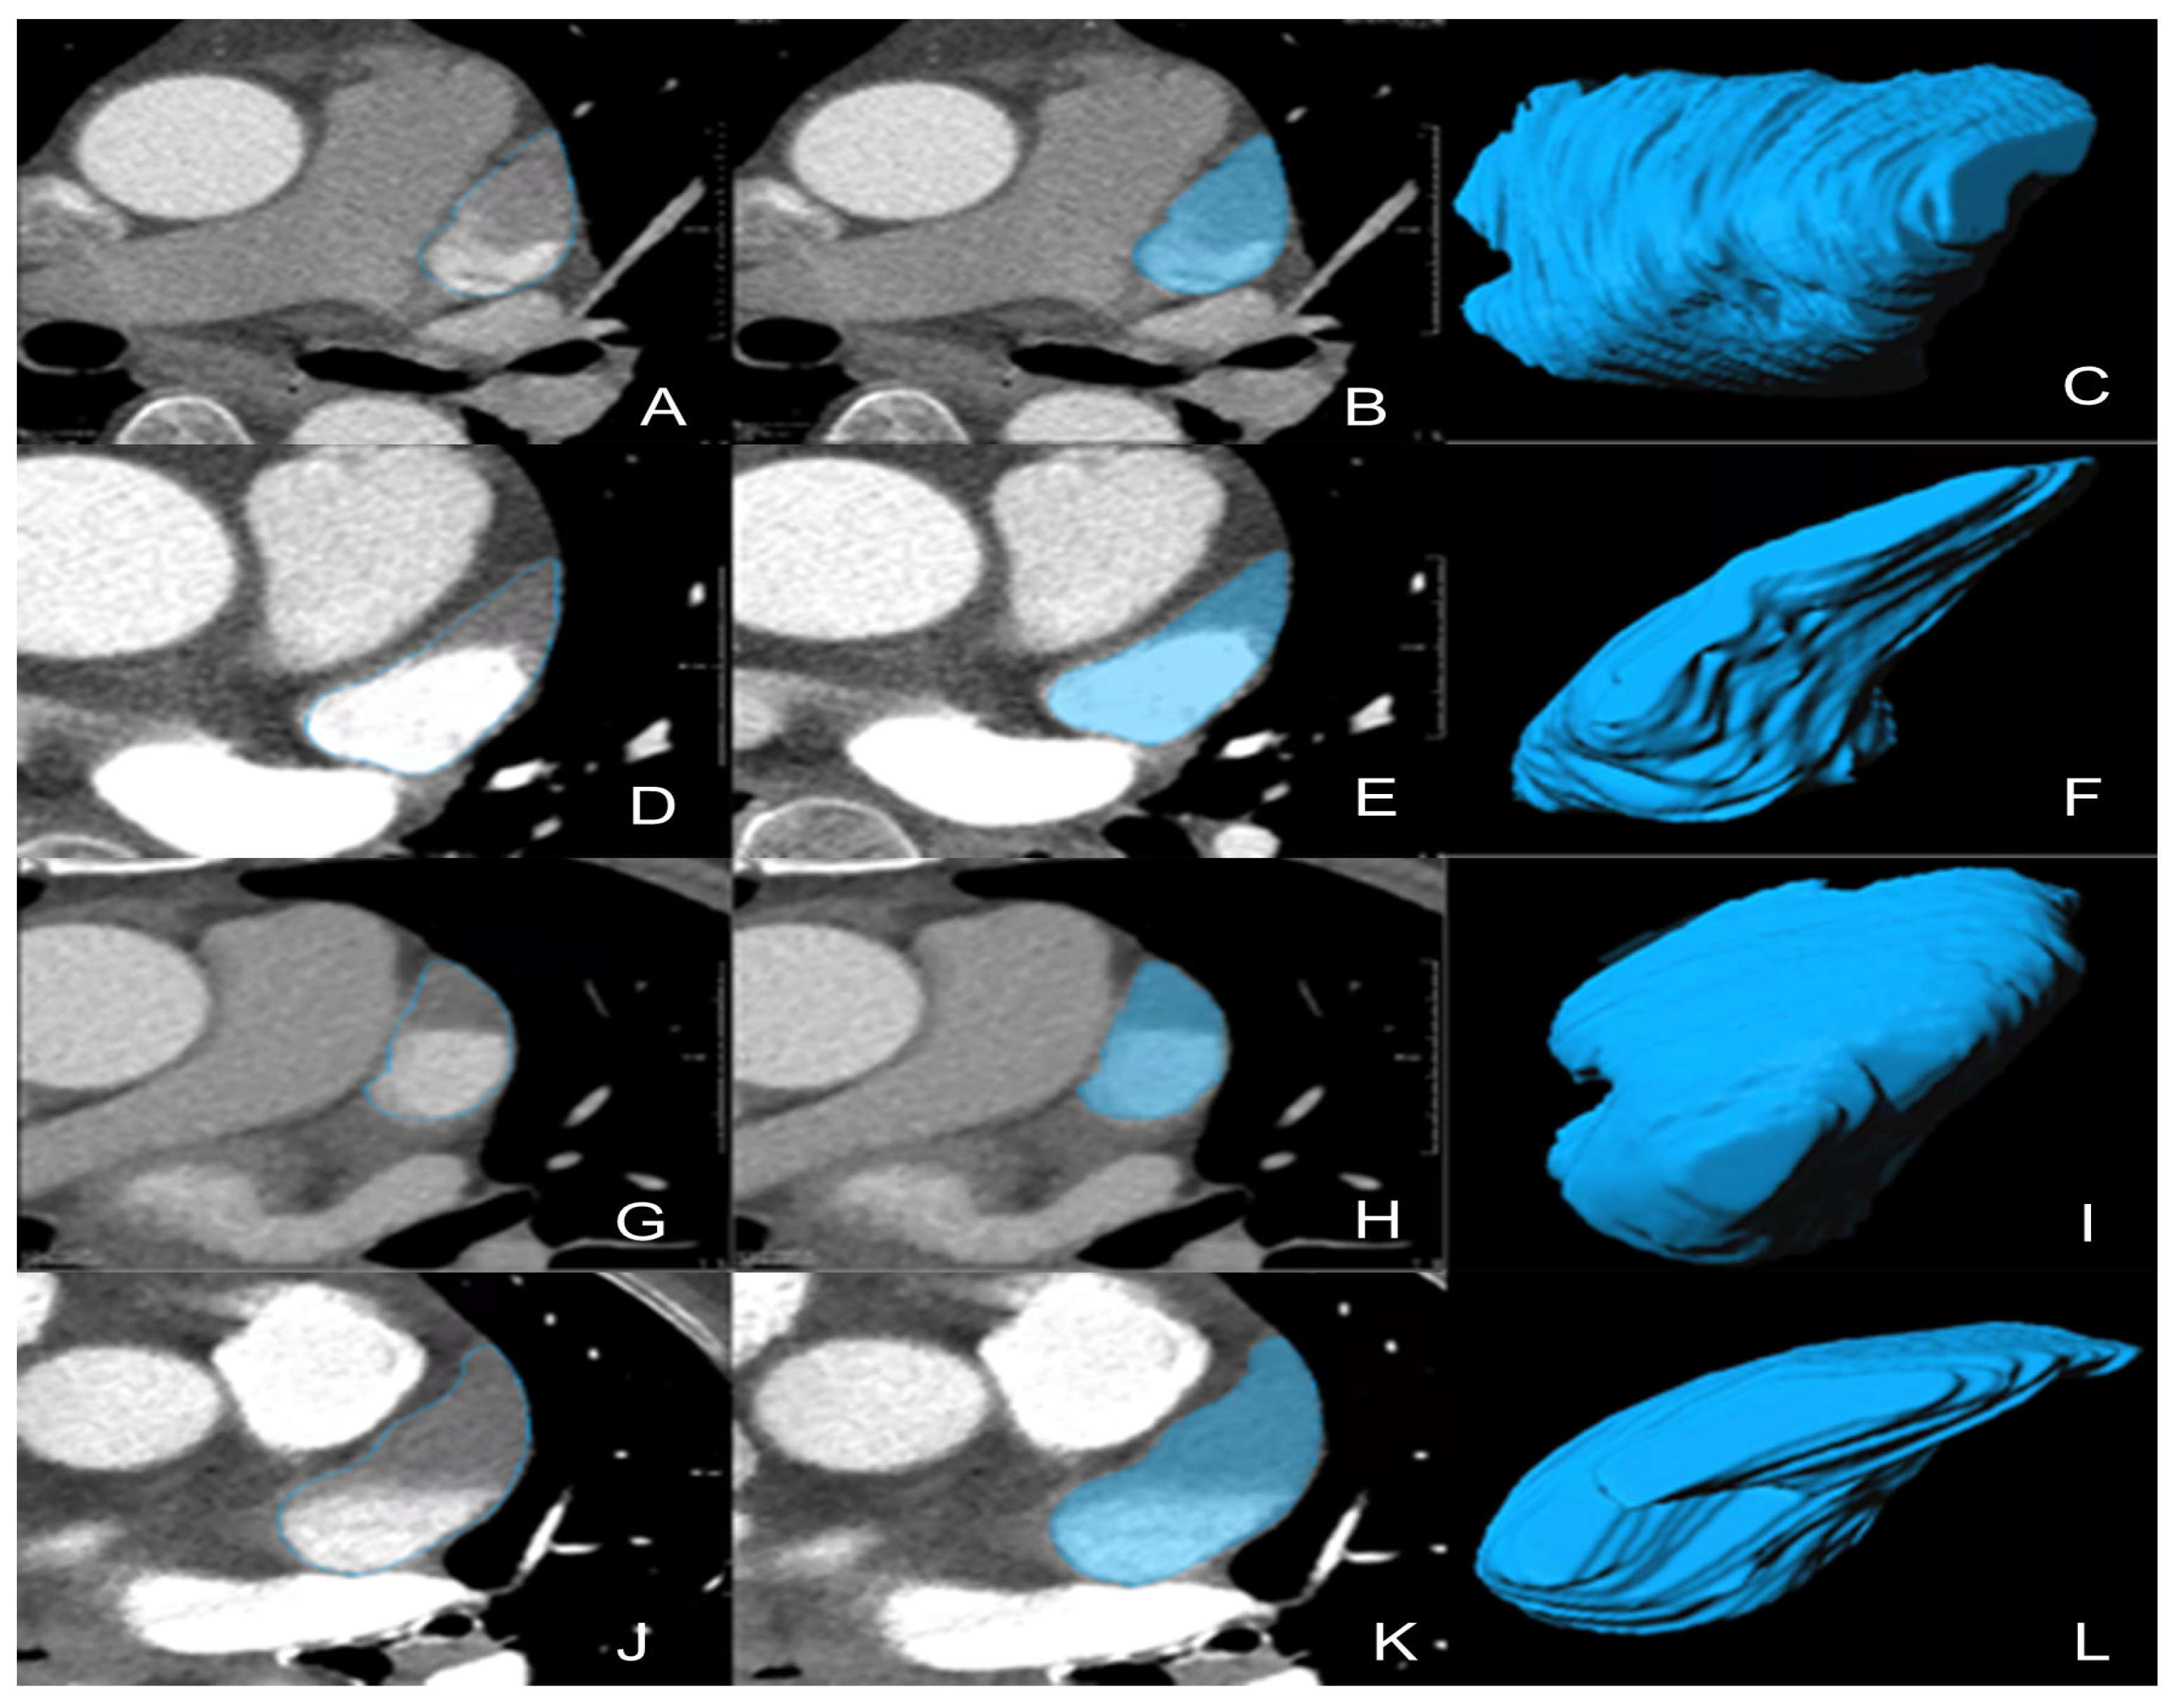

2.4. VOI Segmentation for Radiomics